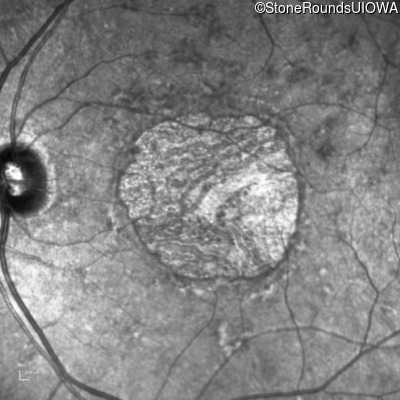

Pattern Dystrophy (IIC)

Age at visit: 47 years

This 47 year man first experienced some decrease in his central vision about 10 years ago.

Diagnosis & molecular findings

Disease Gene Allele 1 variant(s) Allele 2 variant(s) Inheritance mode

Pattern Dystrophy PRPH2 Gly167Asp GGC>GAC   AD